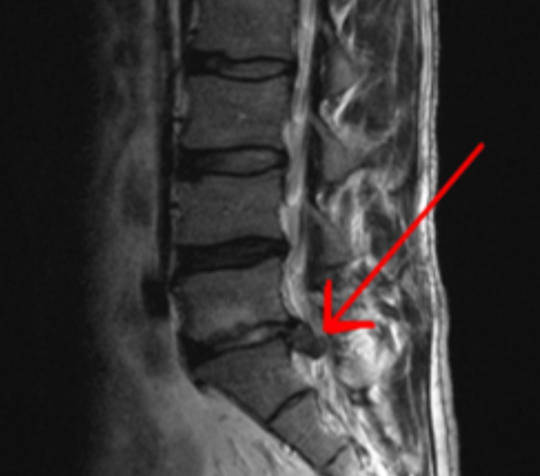

En la fotografía puedes ver como una resonancia realizada en un mismo paciente con dos años de diferencia ante una imagen muy similar las imagenes de resonancia son informadas de una manera distinta.

En la fotografía puedes ver como una resonancia realizada en un mismo paciente con dos años de diferencia ante una imagen muy similar las conclusiones del informe de la resonancia son bastante distintas